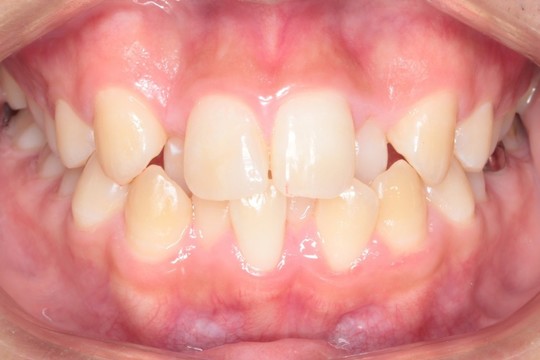

叢生(前歯のデコボコ) 非抜歯矯正

正面 治療前

調布市の20代男性

主訴:前歯のデコボコを直したい

使用装置:インビザライン

治療期間:約2年

治療費用:93.5万円(税込)

治療結果:叢生が改善されました

今回の症例は写真のように上の中心から2番目の歯が左右とも奥に入り込んでいてかなりスペースのない状態でした